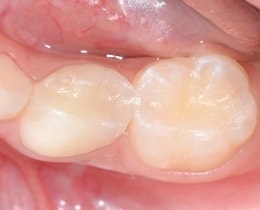

③虫歯の様子

上の部分を削ると、中で虫歯になっている様子がわかります。

このように、上から見えにくい所で、虫歯が進行しています。